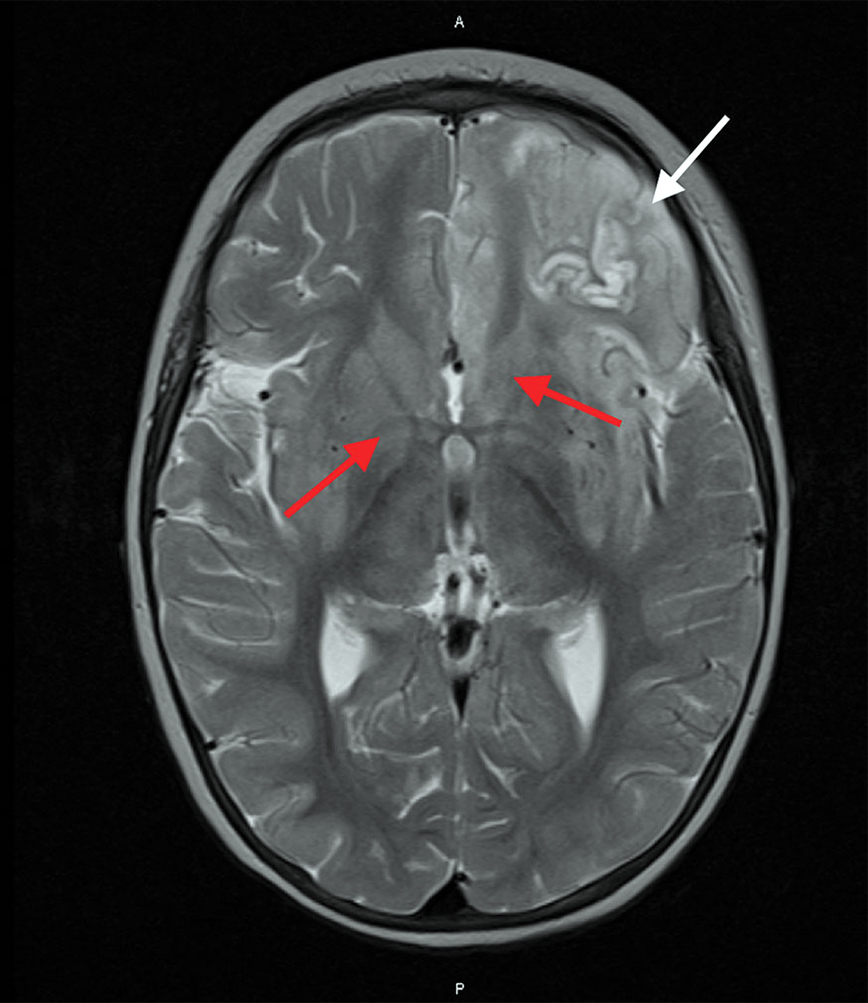

Οι γιατροί πραγματοποίησαν μια σειρά από εξετάσεις, αλλά δεν εντόπισαν οτιδήποτε θα μπορούσε να δώσει απαντήσεις και να εξηγεί το λόγο για τον οποίο η υγεία του παιδιού δεν βελτιωνόταν και το πρήξιμο στον εγκέφαλο δεν υποχωρούσε, παρόλο που του χορηγήθηκε ισχυρή φαρμακευτική αγωγή, που περιελάμβανε αντιικά, αντιβιοτικά και φάρμακα, για να καταπολεμήσει τις επιληπτικές κρίσεις. Κατέληξε 27 ημέρες, αφότου εισήχθη στο νοσοκομείο.

Μετά τον θάνατο του παιδιού, έγιναν εξετάσεις, για να εξακριβωθεί από τι έχασε τη ζωή του και αυτές αποκάλυψαν πως νοσούσε από μια νόσο που προσβάλει τα πτηνά, την APMV-1, η οποία προκαλεί τη νόσο του Νιούκαστλ. Αυτή είναι μια άκρως μεταδοτική νόσος, που επηρεάζει πουλιά και πτηνά, συνήθως περιστέρια. Οι γιατροί, τώρα, υποστηρίζουν πως η μικρή πέθανε από το πρήξιμο του εγκέφαλου, που προκαλεί η προαναφερθείσα νόσος, η οποία άρχισε από τη μύτη ή το στόμα της όταν ήρθε σε επαφή με μολυσμένα περιττώματα περιστεριού ή εκκρίσεις από μολυσμένο περιστέρι.